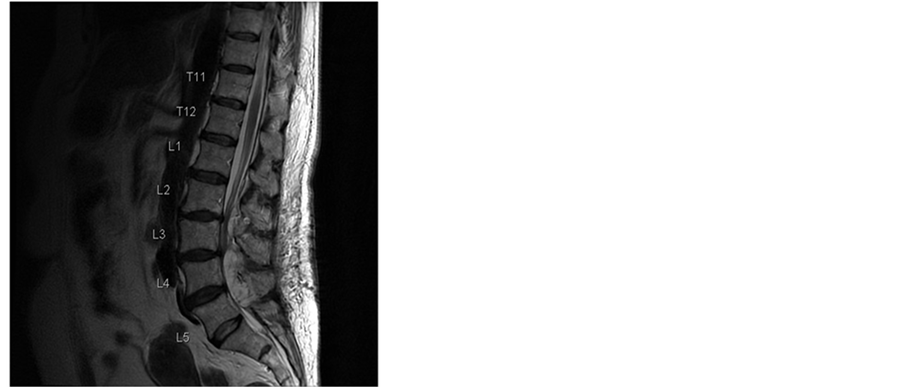

Additionally the patient had various comorbidities in her medical records. The acetylsalicylic acid medication, prescribed from her cardiologist because of a coronary heart disease, was discontinued following our routine protocol 7 days before the surgery was scheduled. The operation itself was uneventful. The patient received general anesthesia with systemic opioid analgesics. An interlaminar access was performed at level L2/3, L3/4 and L4/5, the rezessal nerves were released by removing parts of the ligamentum flavum and the internal surface of the hemi-laminae. Perfect local haemostasis was performed as usual, and no Redon drain was inserted therefore. Due to early mobilization and apart from age no additional risk factors, she got no thrombosis prophylaxis according the 2009 guidelines of the Association of the Scientific Societies in Germany [6] . In the first day the postoperative course was uneventful. The analgesic regime was prescribed according to our local routine, containing opioids, 4 g paracetamol and up to 4 g metamizol in 4 single doses per day and the patient was not anticoagulated to prevent thromboembolic issues. Our patient recovered quickly and the analgesics could be reduced, leaving only metamizol and low dose opioids. The patient was already fully mobilized. On day 3 the local pain increased again and at the same time it became increasingly radicular. Due to calf pain she received 40 mg enoxaparine as a single dose that was stopped thereafter as soon as a deep venous thrombosis was ruled out via compression ultrasound. On the same day we performed an MRI of the spine and discovered a big epidural hemorrhage on L2/3 to L4/5 with compression of the dural sac (Figure 1).

Figure 1. T2-weighted MR images of the lumbar spine 4 days after surgery. Sagittal and axial MR images at L4/5 level demonstrate an acute multisegmental epidural bleeding between L2/3 to L4/5 levels with almost complete obliteration of the spinal canal and severe compression of the dural sac.